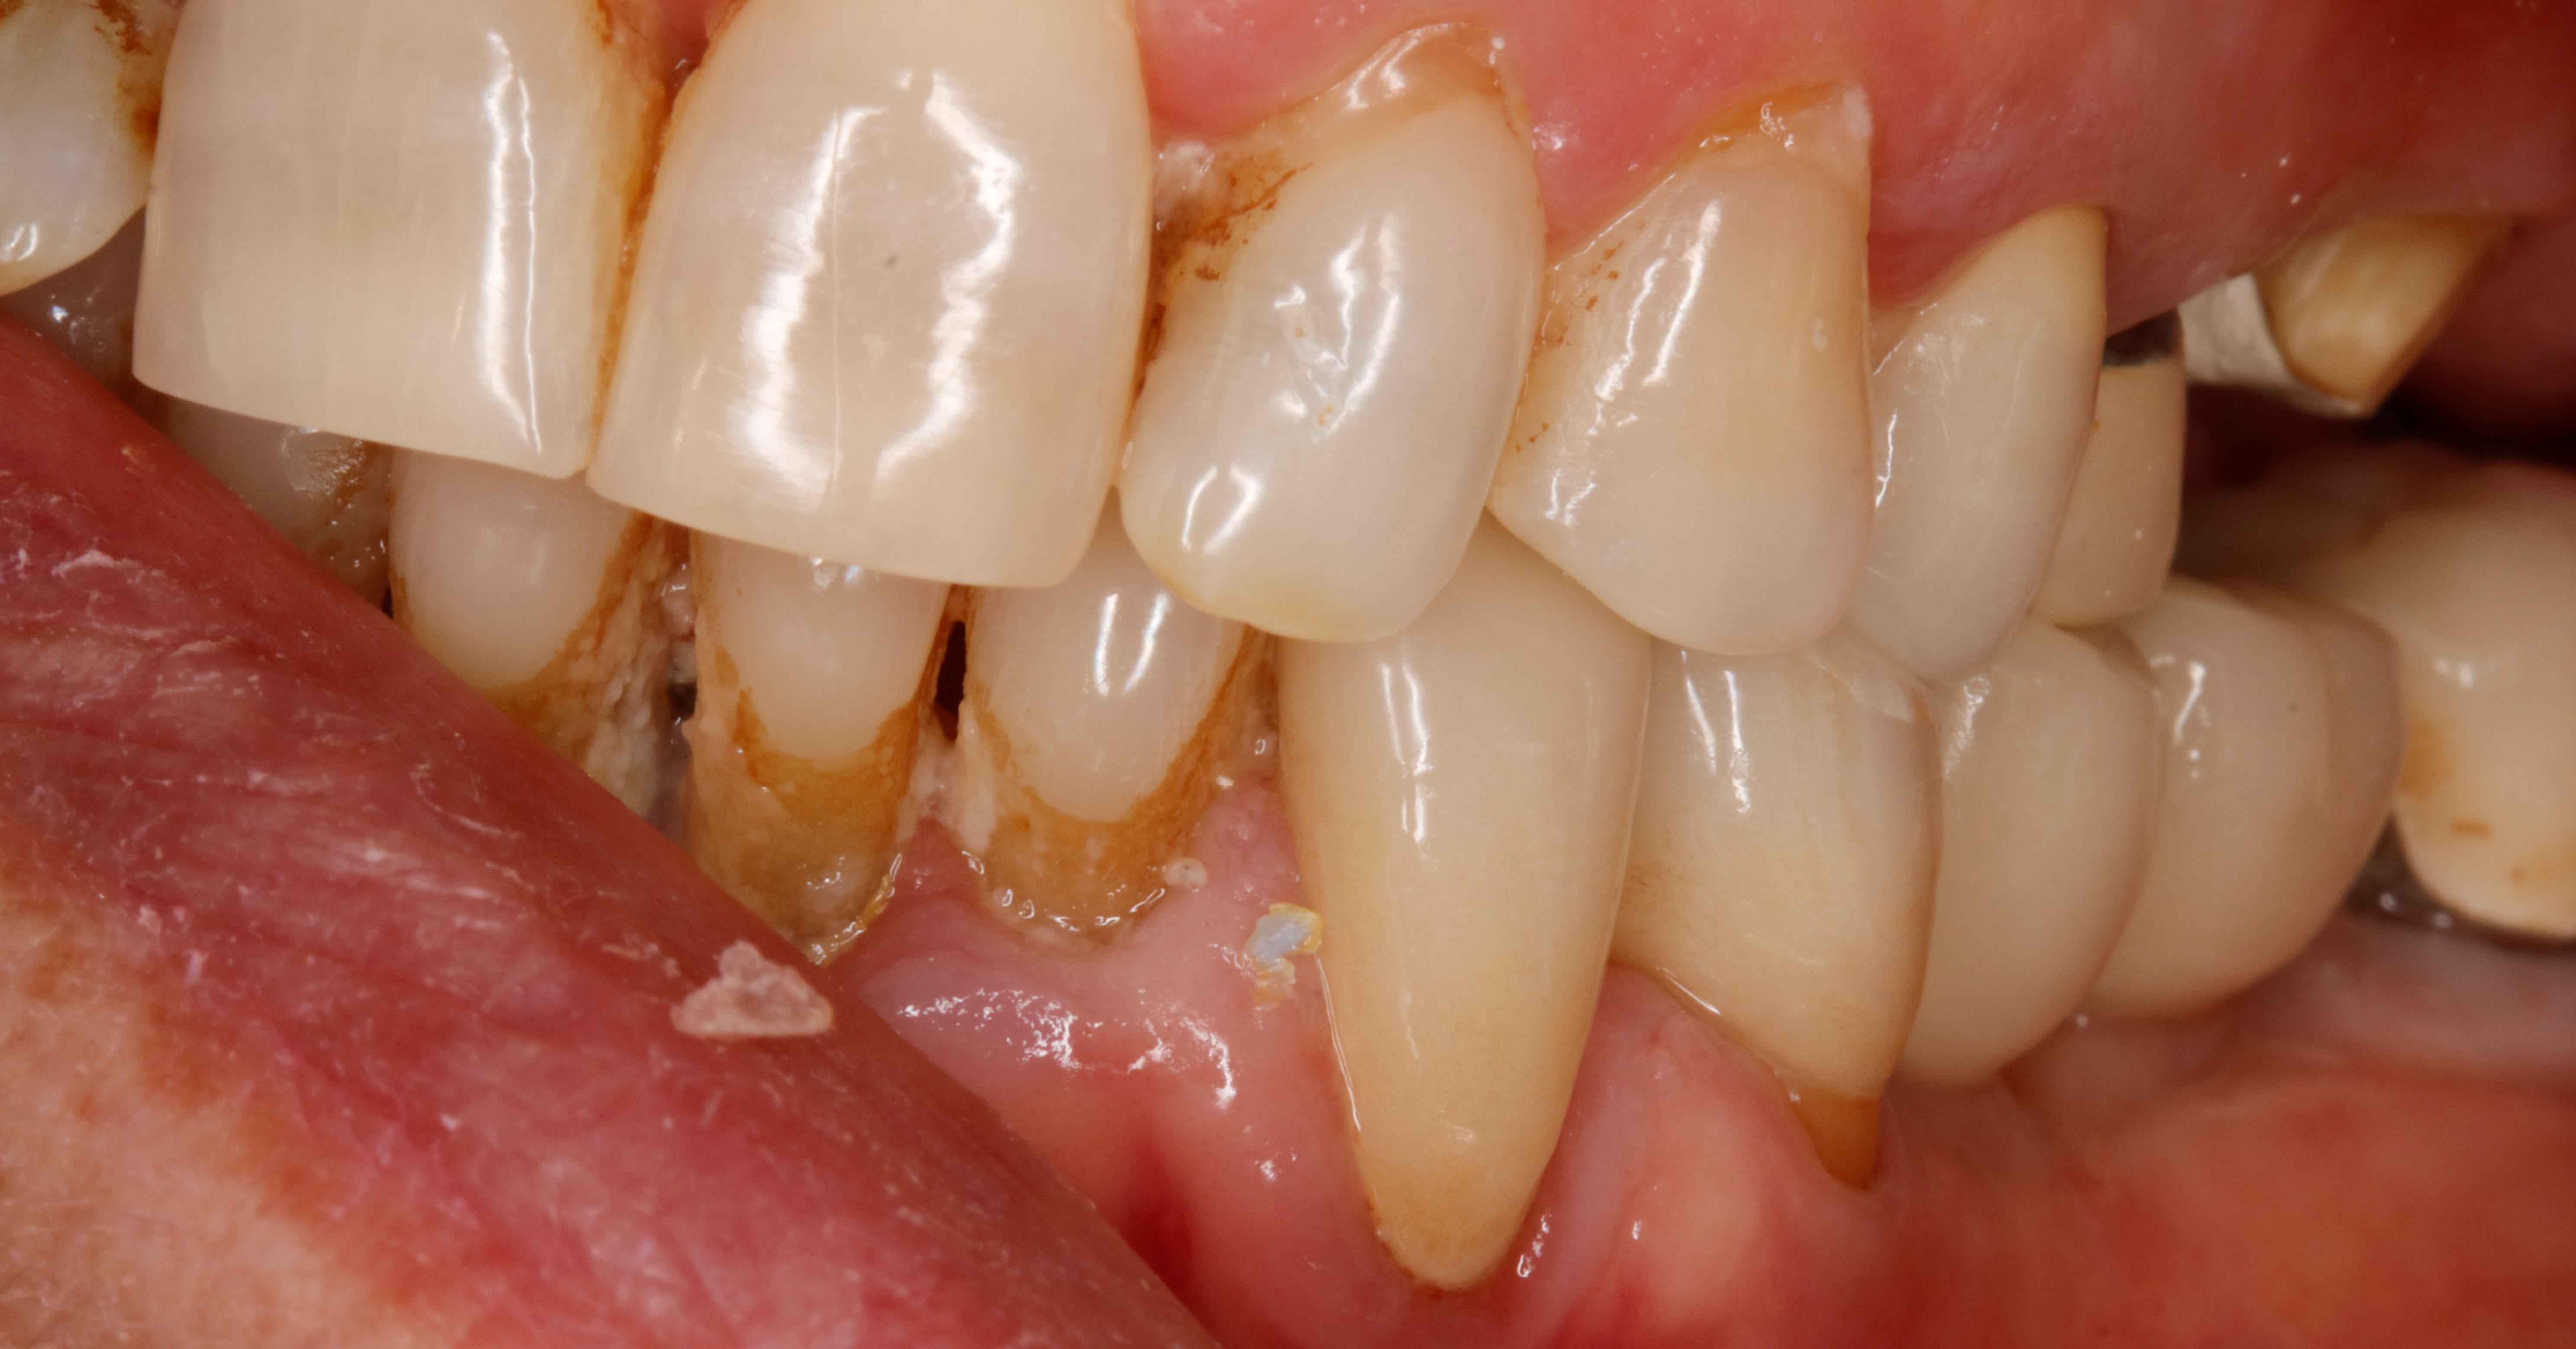

et j en viens à la 2eme chose que je remarque :

ç est que sans contention , sans solidarisation , ça n a pas bronché . je n ai pas perdu un point de contact .

je n ai meme pas eu de fracture de compo au niveau des angles

donc je maintiens que si c est bien équilibré la contention ne sert à rien . meme si c est une occlusion pipée comme ici .

la deuxieme chose , c est que la racine a ete taillée .

et j ai pour habitude de tailler les racines à la grain fin en 1ere intention avec une ligne de finition simple . puis de repréciser la limite en fonction de la cicatrisation .

et quelques fois je la reprécise plus haut ou plus bas , tout dépend de la nouvelle attache .

et meme que souvent je surface les racines des dents d à coté en meme temps ( meme si je ne les couronne pas , hein )

et j ai remarqué que ce cement taillé , bon d abord il est plus lisse , logique , mais plus stable à l étanchéité . pourtant les paro te diront qu il ne faut pas tailler le cement .

enfin , ils le disaient en tout cas , je ne sais pas s ils le disent tjs .

voilà je n en sais pas plus que toi . je constate , c est tout .

ce qui veut dire , que pour un bloc ant comme ici où tout est infiltré pourri .

où il y a égression des dents + perte d os , forcement .

et si je tailles tout , je suis un fou ?? :-)

ça oui , ç est pas nouveau on le sait :-)

mais au final , si il n y a plus de plaque et qu en plus cela permettrait un ajustement occlusal , en plus d etre joli , est ce que serait du sur traitement ?? j 'suis moins sur du coup :-)